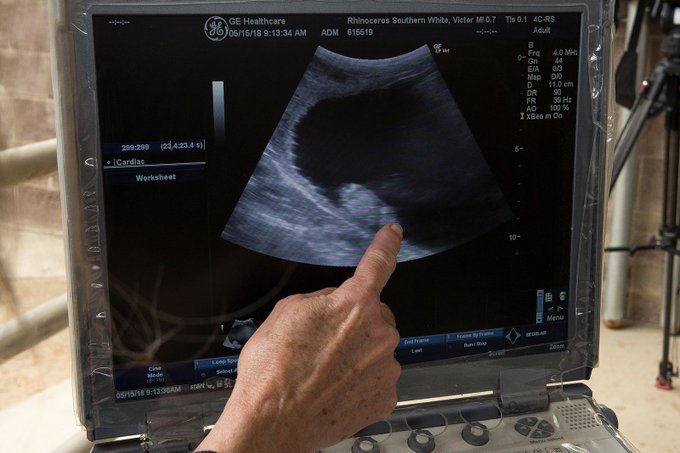

Самку зовут Виктория. В течение 16-18 месяцев, которые продлится ее беременность, носорог будет находиться под пристальным наблюдением.